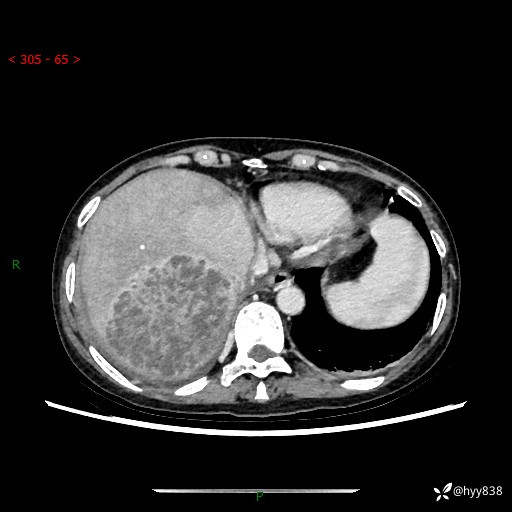

上腹部CT平扫